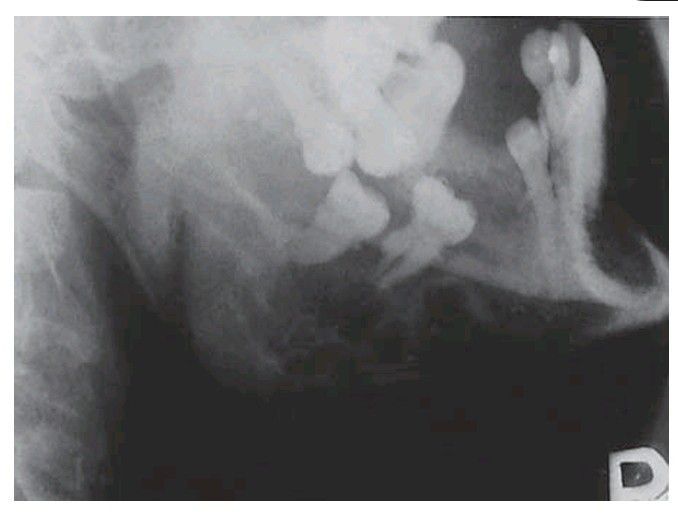

. A patient of 51 with hyperparathyroidism as a result of a parathyroid adenoma. There is an area of bone destruction simulating a multilocular cyst.